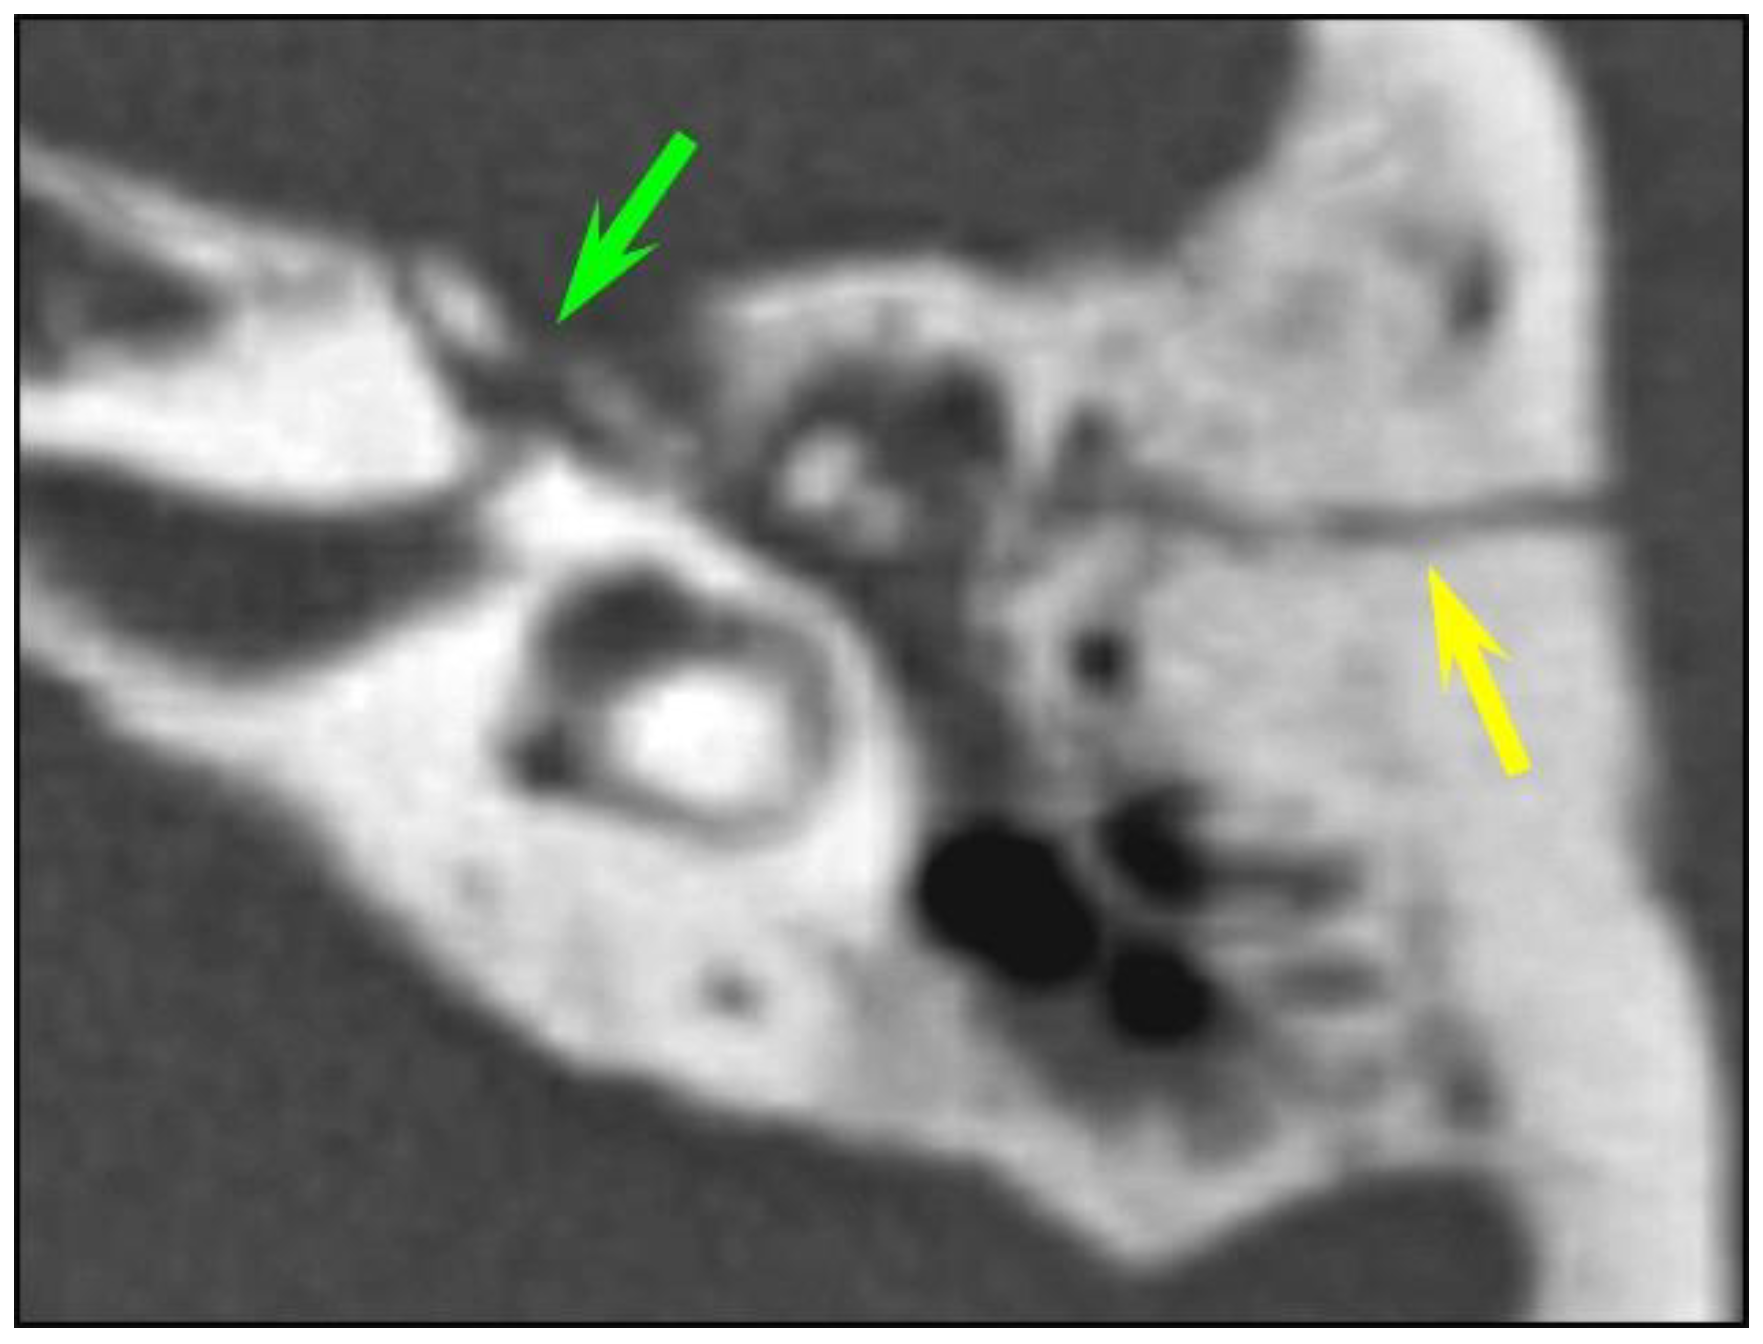

Eleven temporal bone fractures (11/126, 8.7%) showed involvement of the ossicular chain. The incudo-mallear joint was the most frequently injured joint (n = 6), displaying luxation or subluxation (Figure 3). Other injuries were complete incus dislocation (n = 3) and incudo-stapedial luxation (n = 2). Fractures of the tympanic cavity walls were much more common (67/126, 53.2%) than ossicular dislocations. Likewise, fractures of the external auditory canal–temporomandibular joint complex were more common than ossicular chain injuries (91/126, 72.2%).

In our study, ossicular chain injuries were slightly more common in children (13.7%) than in adults (7.7%), and the incudo-mallear joint was the most frequently injured joint in both groups, followed by incus dislocation and incudo-stapedial luxation. Similar results were seen in a case series by Meriot et al. which showed that incudo-mallear joint dislocation was the most common ossicular abnormality (59%), followed by incudo-stapedial joint dislocation (53%) and incus dislocation [17]. As pointed out by different authors, ossicular dislocation can be very subtle. Subluxation of the incus without obvious displacement and with only a minor increase in the space between the articulation surfaces of the incus and malleus can be easily missed on an initial CT scan obtained in an emergency situation. Likewise, the diagnosis of incudo-stapedial luxation can be easily missed unless dedicated 2D oblique reconstructions are obtained. The presence of hemotympanum further hampers ossicular evaluation, especially of the stapes superstructure due to the very small size of the two crura. In our study, most ossicular chain injuries (72.7%) were missed by the resident on call; however, they were detected at a retrospective CT evaluation by specialized head and neck radiologists. Patients with ossicular dislocation typically present with conductive hearing loss persisting several months or years after temporal bone trauma, and the reported delay between the initial injury and diagnosis followed by treatment is within a range of 5–6 years [18]. As post traumatic ossicular dislocation also occurs with head trauma without temporal bone fracture, ossicular disruption should be suspected in all patients with conductive hearing loss persisting after 2-months of the healing process [18]. In these patients, a high-resolution CT is recommended to facilitate diagnosis as the hemotympanum usually resolves 2 months after trauma. Fractures of the malleus, incus or stapes are exceedingly rare and tend to occur after digital manipulation of the external auditory canal or from torsional injuries. As expected, we did not detect any ossicular fractures in this series.

Figure 3. Ossicular chain dislocation. A polytrauma patient with otorrhagia. CT of the left temporal bone (axial plane). (a,b) Longitudinal fracture (yellow arrow); the malleus head (green arrow) is displaced and isolated from the incus body (pink arrow), corresponding to an incudo-malleolar luxation.